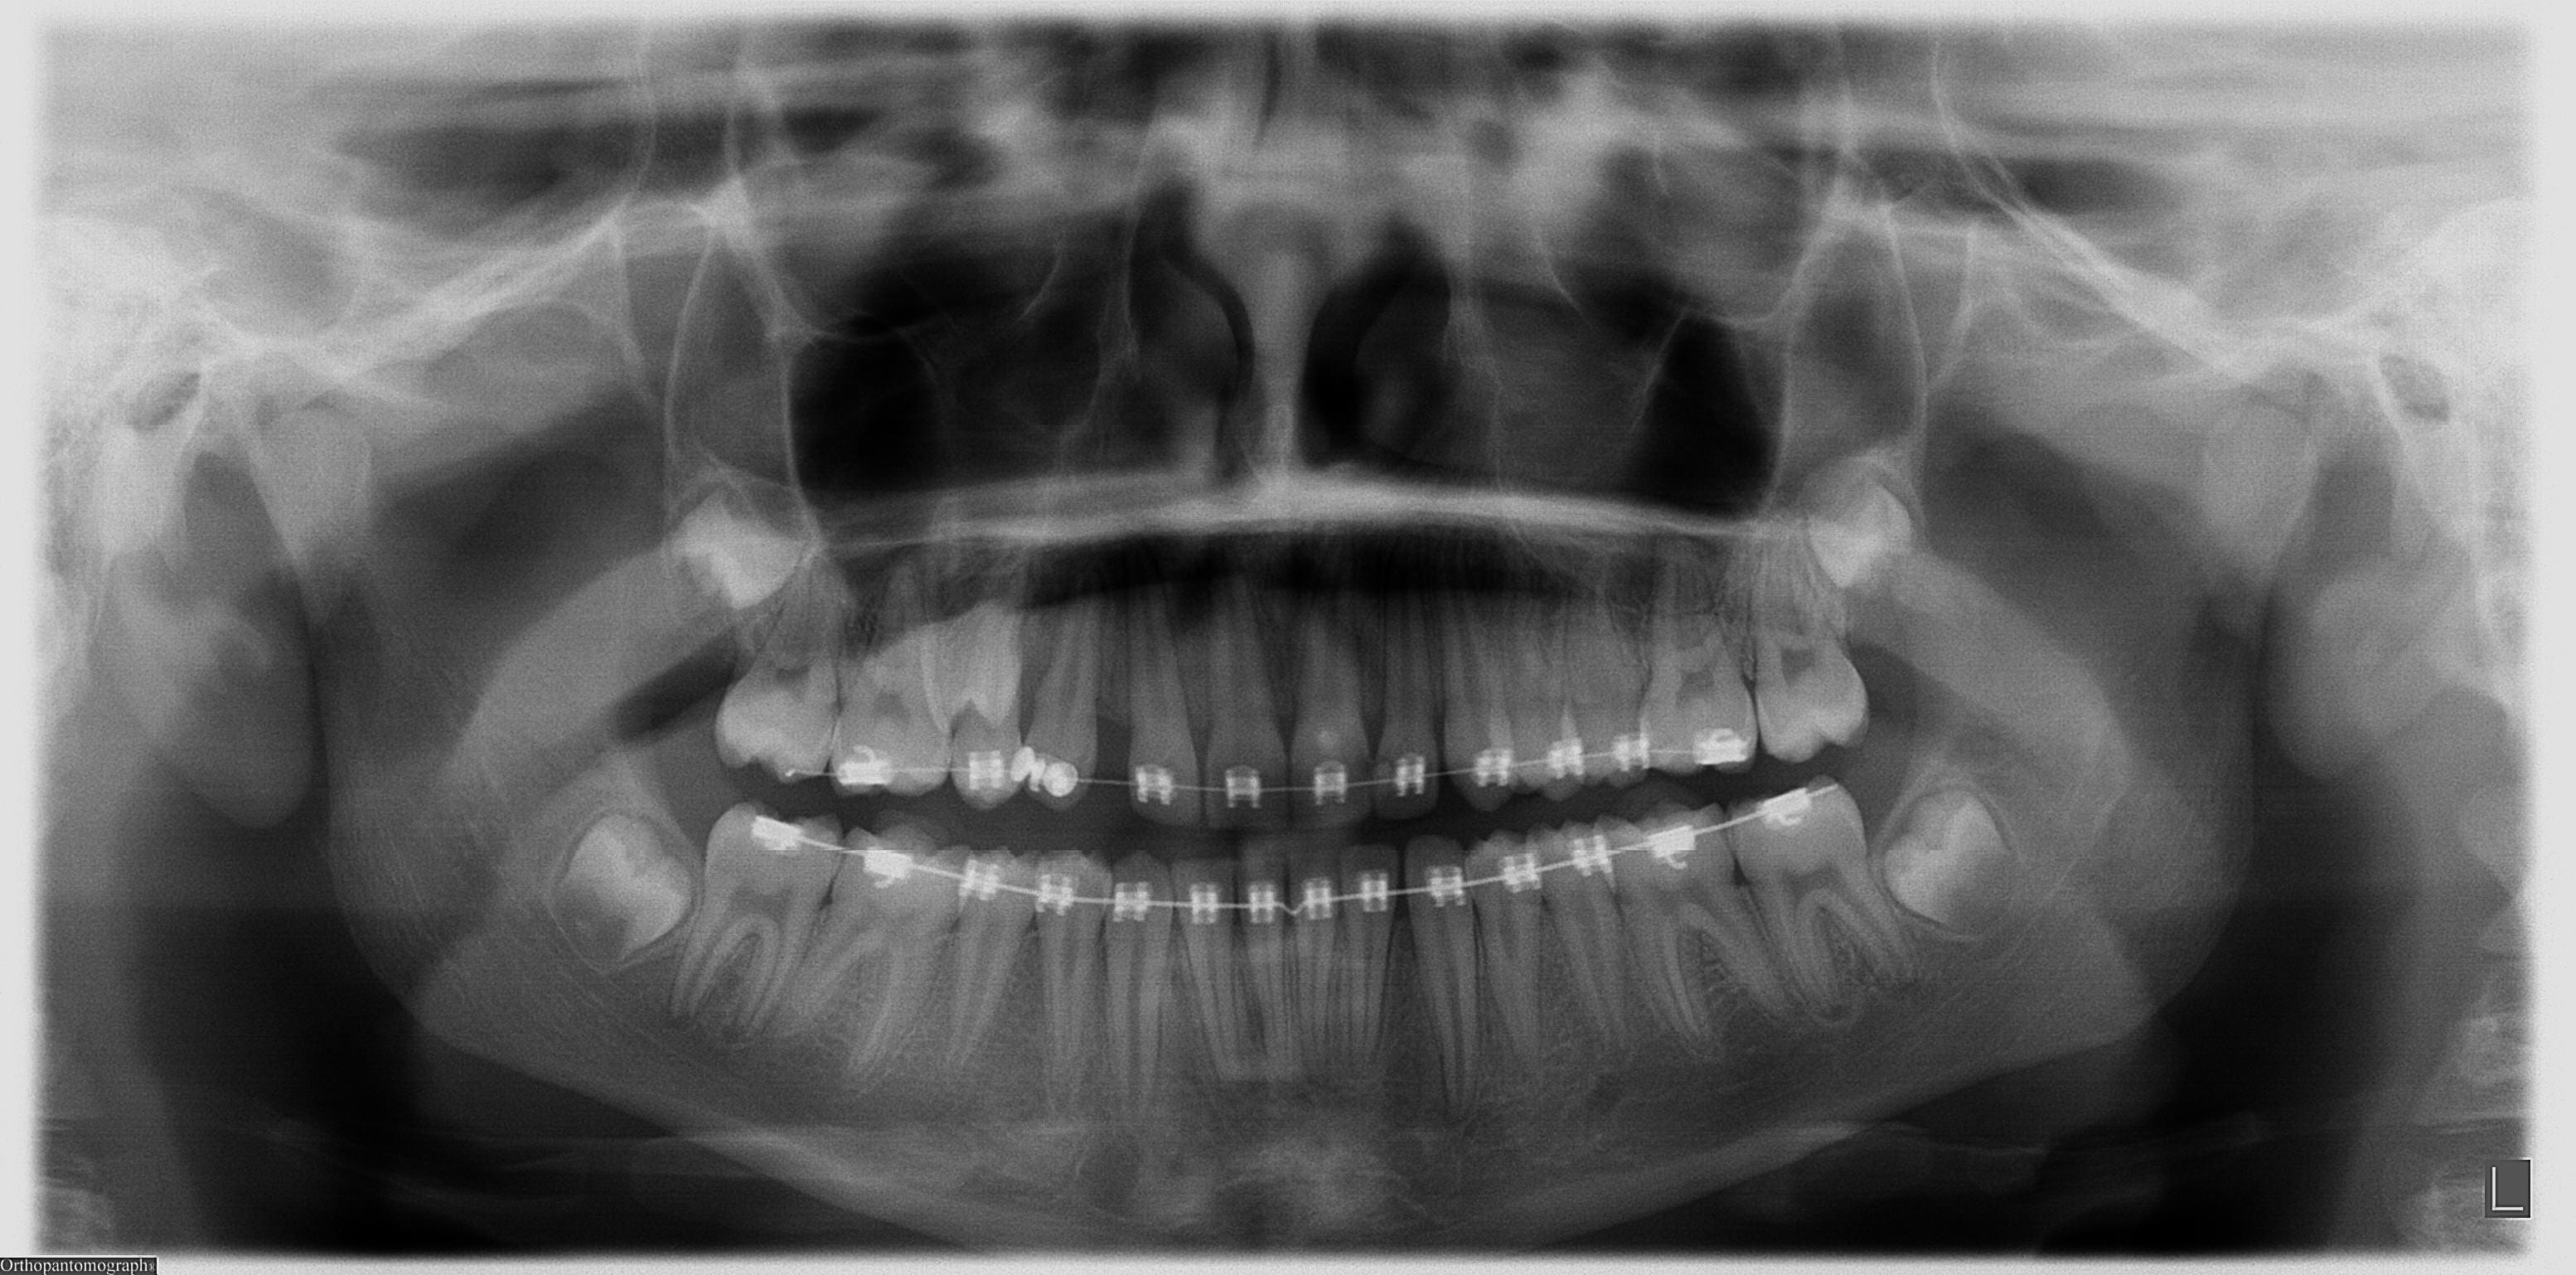

عکس دندان برای ارتودنسی

یکی از کاربرد های عکس دندان در تصمیم گیری و برنامه ریزی جهت درمان ارتودنسی می باشد. عکس دندان در تشخیص اختلالات فک و ضایعات دندانی مفید می باشد.